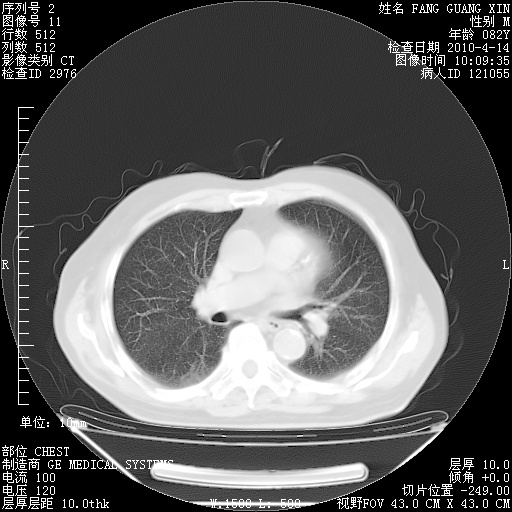

4月14日肺部CT

23.JPG

24.JPG

25.JPG

26.JPG

肺部CT平扫未见异常。